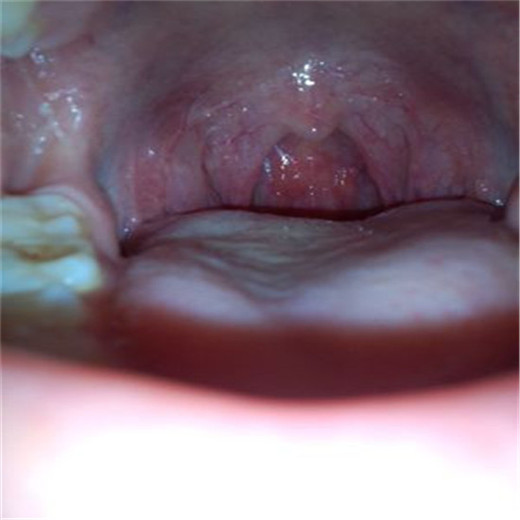

扁桃體炎圖片

扁桃體腫大